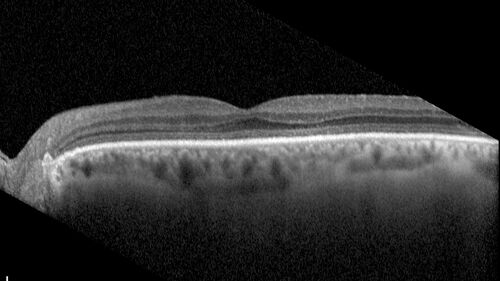

Mild Cone Dystrophy - CRX Mutation

65 year old female with minimal symptoms and a mild cone dystrophy.